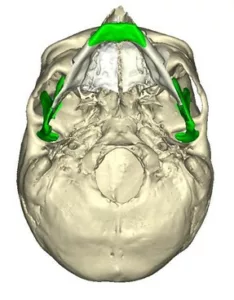

Des miniplaques en titane sur mesure spécifiques de l’anatomie propre à chaque patient et spécifiques des mouvements envisagés par le chirurgien permettent de stabiliser toutes les pièces anatomiques libérées par les manœuvres d’ostéotomie conformément à la simulation : plateau maxillaire, arc denté mandibulaire, branches montantes et condyles, menton .

Ostéotomie de Lefort I en 1, 2 ou 3 fragments, ostéotomie sagittale des branches montantes, génioplasties, ostéotomies segmentaires maxillaires et mandibulaires, postérieures ou antérieures, plus rarement ostéotomies de Lefort II ou Lefort III, tous les types d’ostéotomies peuvent être réalisés en chirurgie guidée.